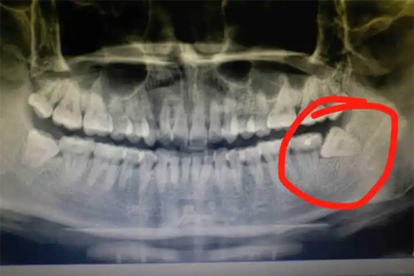

少数情况下如下午就诊时间紧张、患者存在高血压或糖尿病未控制、智齿埋伏较深伴发感染时,医生可能建议改期至上午操作。这类情况需优先控制基础疾病,并预留足够术后观察时间。